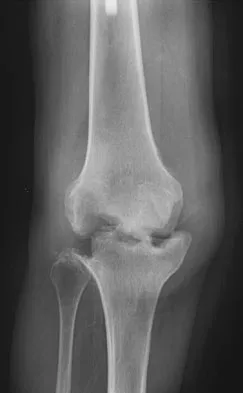

Question 67 High Yield

A 32-year-old laborer reports left ankle pain and deformity. History reveals that he sustained a left ankle fracture 2 years ago and was treated with closed reduction and casting. Radiographs are shown in Figures 25a through 25c. What is the most appropriate management?

Detailed Explanation

Corrective osteotomy of fibular malunions, with appropriate lengthening, even in the presence of early arthritis, has been shown to decrease ankle pain and increase stability. Reduction and bone grafting of the medial malleolar nonunion is also needed. There is no evidence supporting the use of intra-articular steroids or hyaluronic acid in the ankle joint. Lateral talar displacement of even 1 mm has been reproducibly shown to decrease tibiotalar contact by 40% to 42%, causing a predisposition to arthritis. Weber D, Friederich NF, Muller W: Lengthening osteotomy of the fibula for post-traumatic malunion: Indication, technique and results. Int Orthop 1998;22:149-152. Lloyd J, Elsayed S, Hariharan K, et al: Revisiting the concept of talar shift in ankle fractures. Foot Ankle Int 2006;27:793-796. Offierski CM, Graham JD, Hall JH, et al: Later revision of fibular malunion in ankle fractures. Clin Orthop Relat Res 1982;171:145-149.